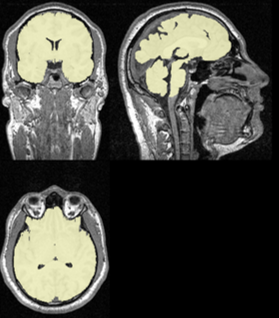

Figure 1: Left – Slice of an MRI scan with previews from Coronal (top left), Sagittal (top right), and Axial (bottom) planes. Right – The corresponding segmentation masks.

In order to derive reliable results from MRI data, a pipeline constituting multiple steps is required. One of these steps is Brain Extraction (also known as Skull Stripping), where the skull and other unwanted artifacts are removed from the scan; leaving behind only the brain. This allows the researchers to further process the brain scans without interference from the unwanted parts of the original scan.

We consider brain extraction as an instance of the Semantic Segmentation problem from the field of Computer Vision. That is, a function that implements brain extraction receives a scan as input and returns a binary mask where each pixel is either marked as brain or unwanted background.